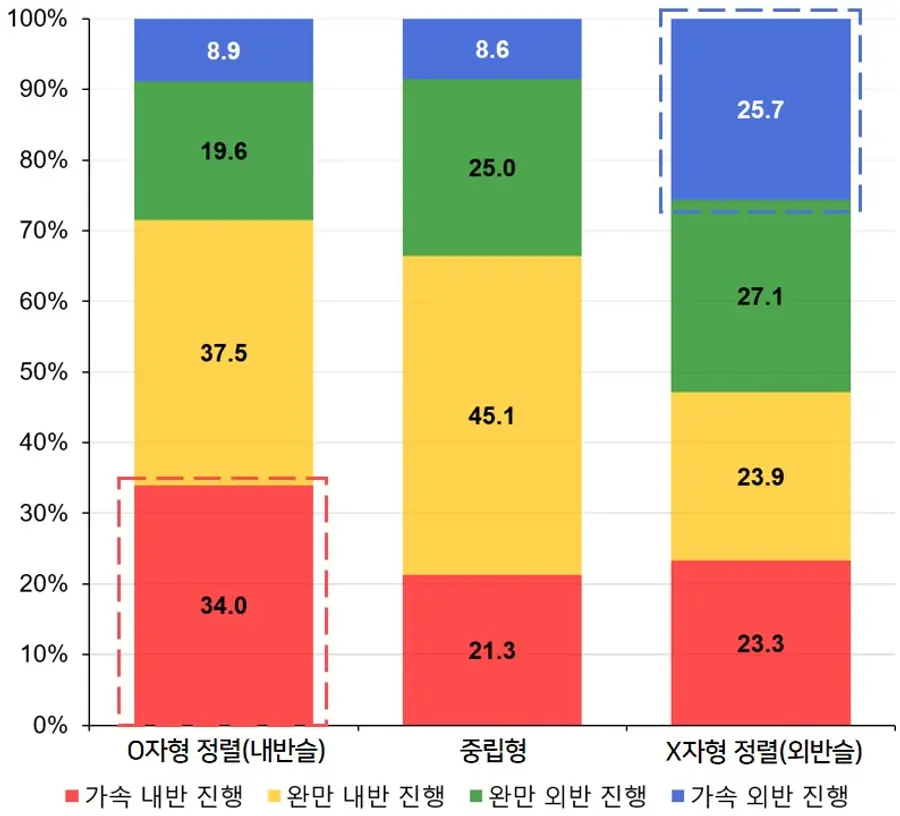

연구팀은 인공지능 기반 소프트웨어를 활용해 환자의 하지 엑스레이 사진을 분석했다. 이를 통해 엉덩이-무릎-발목 각도(HKAA), 관절선 수렴각(JLCA), 관절염 중증도(K-L 등급) 등 주요 지표를 측정했다. 다리가 휘어진 정도인 HKAA를 기준으로 하지를 ▲O자형 ▲중립 ▲X자형으로 구분하고, 정렬 변화가 연간 0.5° 이상인 경우를 ‘가속 진행’으로 정의해 정렬 변화 양상과 영향 요인을 분석했다.

분석 결과, 무릎 정렬은 전반적으로 O자형 방향으로 진행되는 경향이 더 흔하게 나타났다. 특히 O자형 정렬 집단의 34.0%와 X자형 정렬 집단 25.7%에서 정렬이 빠르게 악화되는 가속 진행이 확인됐다.